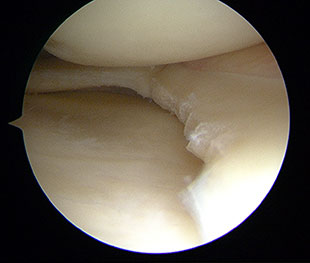

Die Operation am Meniskus wird arthroskopisch durchgeführt. Dabei werden die Instrumente über mehrere kleine Einschnitte in das Kniegelenk eingeführt. Der Operateur verfolgt den Eingriff auf einem Bildschirm. Im Rahmen der Arthroskopie ist eine exakte Beurteilung der Meniskusverletzung hinsichtlich Lage und Ausdehnung von Meniskusrissen möglich. In Abhängigkeit von der Art der Meniskusverletzung können eingerissene Anteile entfernt oder mittels Nahttechniken

MENISKUSREFIXATION

Frische Verletzungen, insbesondere wenn sie basisnah, das heißt nahe der Kapsel gelegen sind, können mit speziellen Techniken refixiert werden. Zur Verfügung stehen verschiedene Nahttechniken, die in den letzten Jahren weiterentwickelt worden sind und nicht wieder entfernt werden müssen, z.B. die Meniskusrefixation über eine Meniskusnaht.

MENISKUSTEILRESEKTION

Ist eine Refixation des eingerissenen Meniskus nicht möglich, wird nur der Meniskusanteil entfernt, der wirklich eingerissen bzw. instabil ist (Meniskusteilresektion). Eine komplette oder nahezu vollständige Entfernung des Meniskus sollte unbedingt vermieden werden.